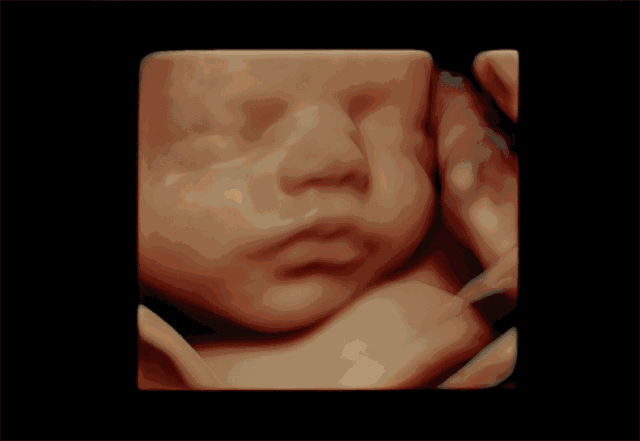

四维彩超的全称是四维彩色超声诊断仪,是世界上先进的彩色超声设备。

四维彩超能够更加清晰的筛查胎儿在子宫的状态,筛查胎儿是否有异常,提供准确的科学依据,及早发现、及早作出解决方案。

四维彩超除了是准妈妈和BB的“第一次”见面,能够看到ta在肚子里或活泼或文静的可爱模样,重要的是能够监测到胎宝宝的健康情况,进行排畸检查,所以也叫胎儿畸形筛查,是孕期特别重要的一次超声检查。